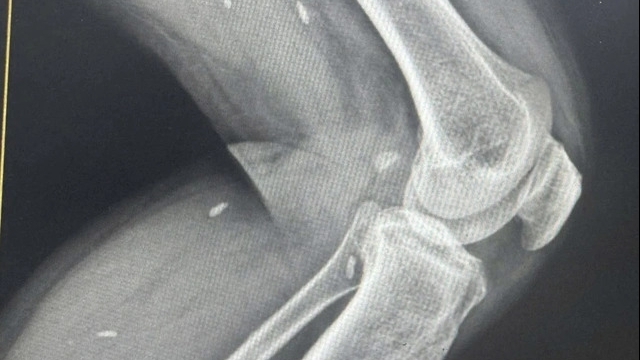

Hình ảnh Cắt Lớp Vi Tính: khối cholesteatoma ăn mòn xương con và lan rộng trong tai giữa trái

Tại đây, các bác sĩ cho bé nội soi tai, đo các test thăm dò chức năng tai và chụp cắt lớp vi tính tai xương đá. Kết quả phát hiện khối bất thường trong tai giữa lan rộng và hình ảnh mất liên tục hệ thống xương con trong tai giữa bên trái, sức nghe tai trái giảm khá nhiều nên bé chỉ nghe rõ được âm thanh bằng tai phải.

Khối Cholesteatoma ăn mòn xương con trong tai giữa

Sau 5 giờ phẫu thuật, khối cholesteatoma ăn mòn xương trong tai giữa trái đã được lấy sạch và kiểm soát tốt. Các phẫu thuật viên nhận định “Đây là một trường hợp khó và hiếm gặp, bệnh nhi rất may mắn khi được phát hiện và phẫu thuật kịp thời, vì nếu để lâu hơn thì khối cholesteatoma có thể phá hủy xương lan rộng gây liệt mặt, gây chóng mặt và điếc tai trong không hồi phục và nguy hiểm hơn nữa là lan lên não gây viêm màng não, áp xe não nguy hiểm đến tính mạng”.